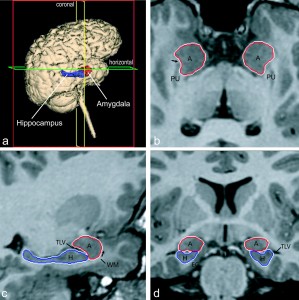

Amigdala e ippocampo